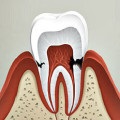

Fissure fogszuvasodás - a kóros folyamat, hogy fejleszti a fogat mélyedések (fissura). Az utóbbi lehet a különböző formák - nyitott (vagy fodrozott kúp alakú) és zárt (csepp alakú). A legtöbb betegség érinti a 6. és a 7. foga. Mint egyéb kóros folyamat, ez ahhoz vezethet, idegkárosodás és kemény fogak szövetekben.

Vizuálisan a betegség könnyen azonosítható egy adott sötétedő üreget. Különösen könnyű ezt egy nyitott hasadék.